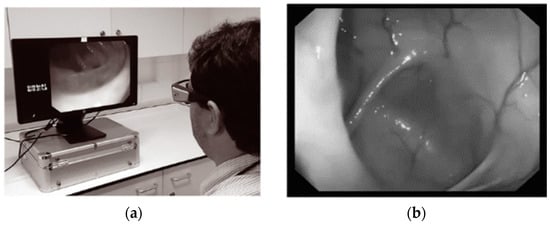

3.1. NET in Endoscopy

| [54] | 2007 | Endoscopy | VOG | Headcoil | Wired | - | 50 |